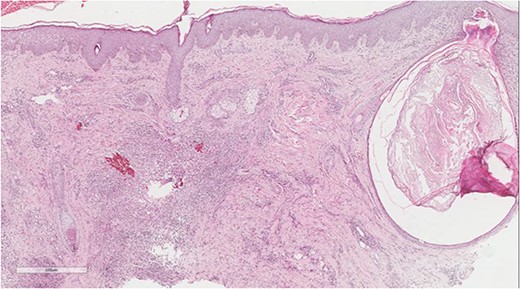

A 5 mm skin punch biopsy was also taken from the neck. Histopathology showed cystically dilated hair follicle with surrounding fibrosis and heavy inflammatory infiltrate and granulation tissue (Fig. 1), the inflammatory infiltrate is composed of lymphocytes, plasma cells, neutrophils and histiocytes (Fig. 2). The overall morphologic picture was suggestive of follicular occlusion syndrome (Fig. 3). A diagnosis of HS was made, and the patient was started on rifampin 600 mg OD and clindamycin 300 mg BID. A lipid panel was ordered as well and showed a triglyceride level of 1.99 mmol/L (0.7–1.7 mmol/L).

Dilated hair follicle with perifollicular inflammation and adjacent foreign body giant cell reaction secondary to ruptured dilated hair follicle in a background of dermal fibrosis.